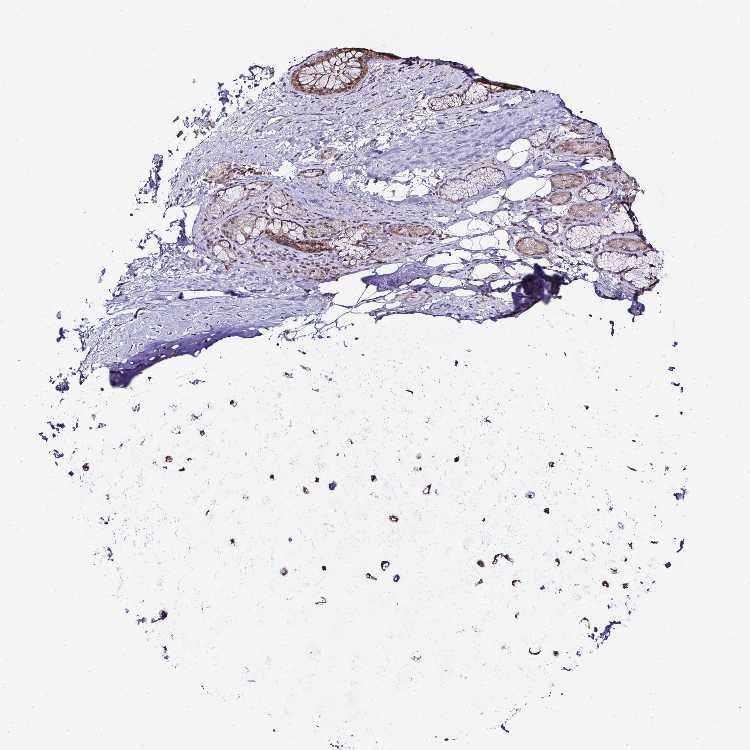

ADIPOSE TISSUE - Antibody stainingi

Antibody staining in the annotated cell types in the current human tissue is reported as not detected, low, medium, or high, based on conventional immunohistochemistry profiling in selected tissues. This score is based on the combination of the staining intensity and fraction of stained cells.

Each image is clickable and will lead to virtual microscopy that enables deeper exploration of all samples and also displays staining intensity scores, fraction scores and subcellular localization as well as patient and tissue information for each sample.

Antibody HPA047478Antibody HPA055752Antibody CAB008678

Adipocytes Not detectedNot detectedNot detected